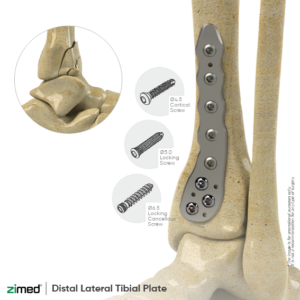

Locking Distal Lateral Tibial Plate

-